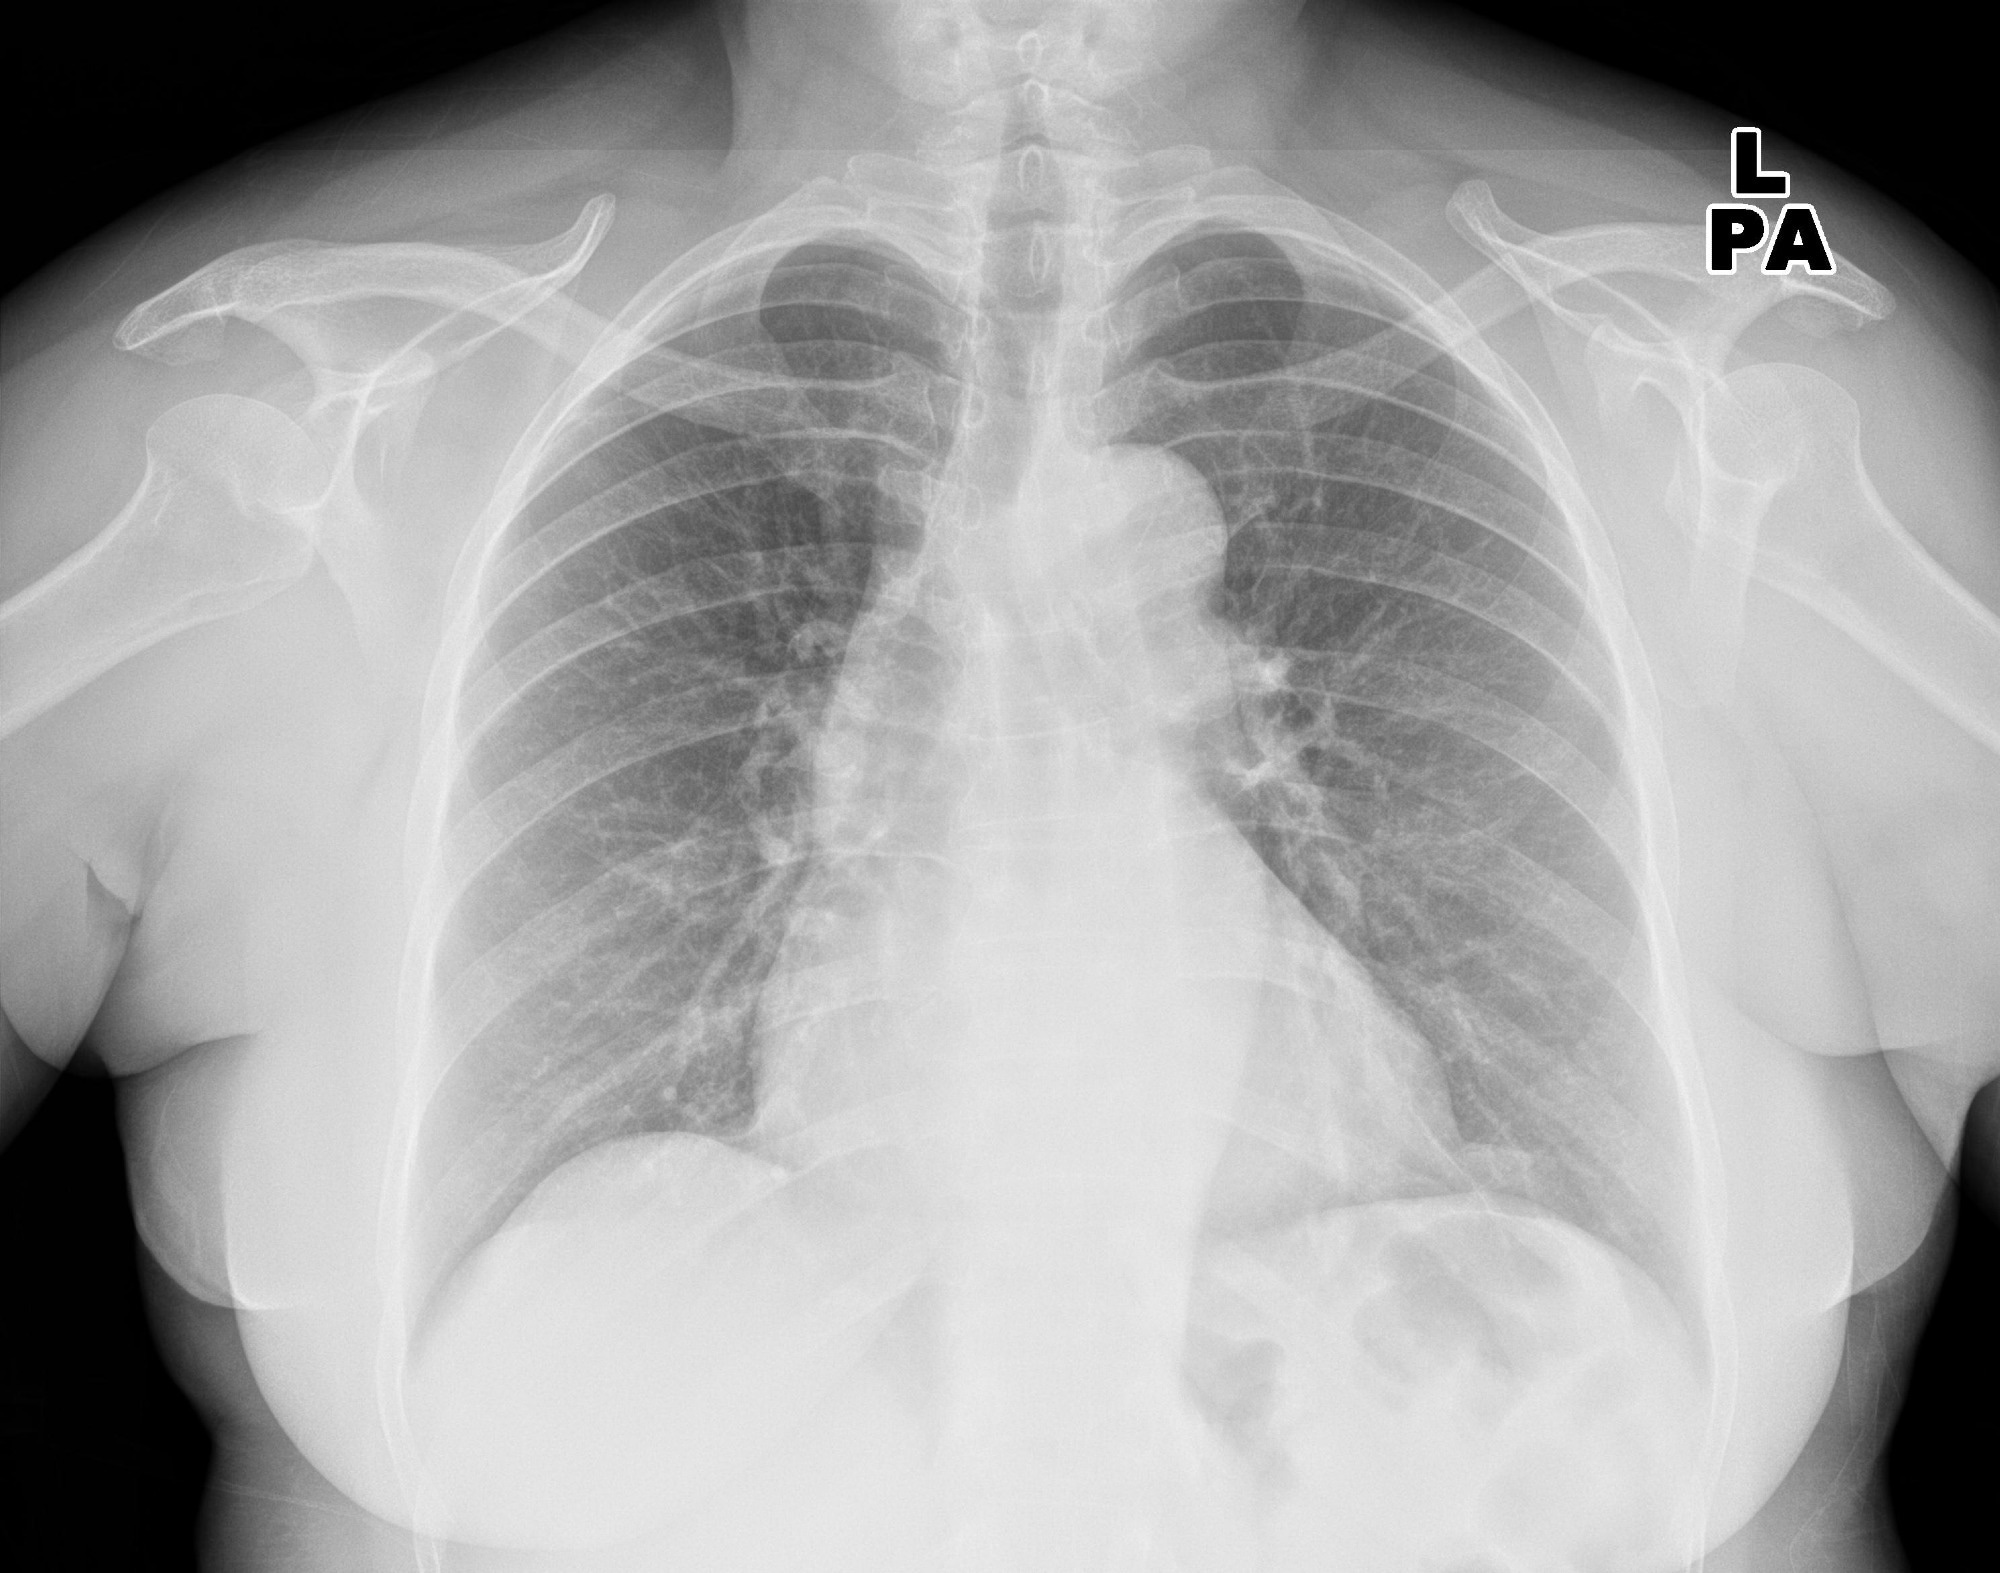

In a recent study published in the journal Radiology, researchers evaluated the diagnostic accuracy of four artificial intelligence (AI) tools in detecting pleural effusion, airspace disease, and pneumothorax on chest radiographs.

Study: Commercially Available Chest Radiograph AI Tools for Detecting Airspace Disease, Pneumothorax, and Pleural Effusion. Image Credit: KELECHI5050 / ShutterstockStudy: Commercially Available Chest Radiograph AI Tools for Detecting Airspace Disease, Pneumothorax, and Pleural Effusion. Image Credit: KELECHI5050 / Shutterstock

Radiographs were analyzed for airspace disease, pleural effusion, and pneumothorax. Experienced thoracic radiologists blinded to AI predictions performed the reference standard assessment. Two readers independently labeled chest radiographs. Readers had access to patients' medical history, including their prior or future chest radiographs or computed tomography (CT) scans.

Airspace disease, pleural effusions, and pneumothorax were identified on 393, 78, and 365 chest radiographs upon reference standard examination, respectively. An intercostal drainage tube was present in 33 patients. Sensitivities and specificities of AI tools were 72% to 91% and 62% to 86% for airspace disease, 62% to 95% and 83% to 97% for pleural effusion, and 63% to 90% and 98% to 100% for pneumothorax, respectively.